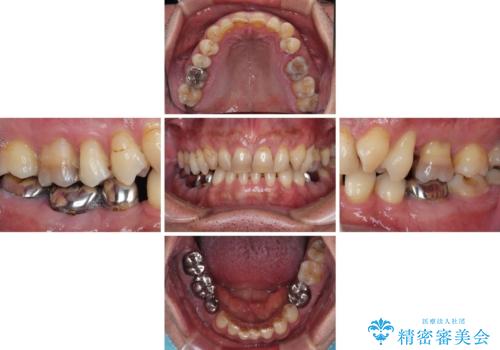

- 薬剤の影響で黄ばんでしまった前歯を気にして来院された患者様です。

お子様が大学を卒業され、経済的に余裕ができたとのことで、長年気にしていた前歯を綺麗にする決断をされたとのことでした。

奥歯の銀歯も気にはなるものの、口を開けたときに目立たないとのことで、上下ともに前歯を中心にオールセラミッククラウンにて補綴治療を行うこととしました。